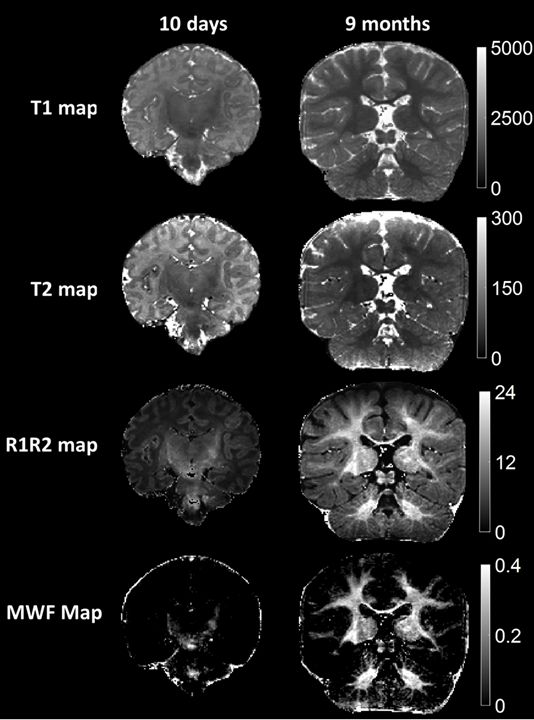

Figure 5: Comparison of the quantitative MRF maps from babies aged 10 days and 9 months. The images demonstrate differences in the maturation of brain structure as well as the progression of myelination. The neonatal maps demonstrate myelination of corona radiata, internal capsule and superior cerebellar peduncles, while the 9 month infant maps show progression of myelination more diffusely in the supratentorial and infratentorial white matter.